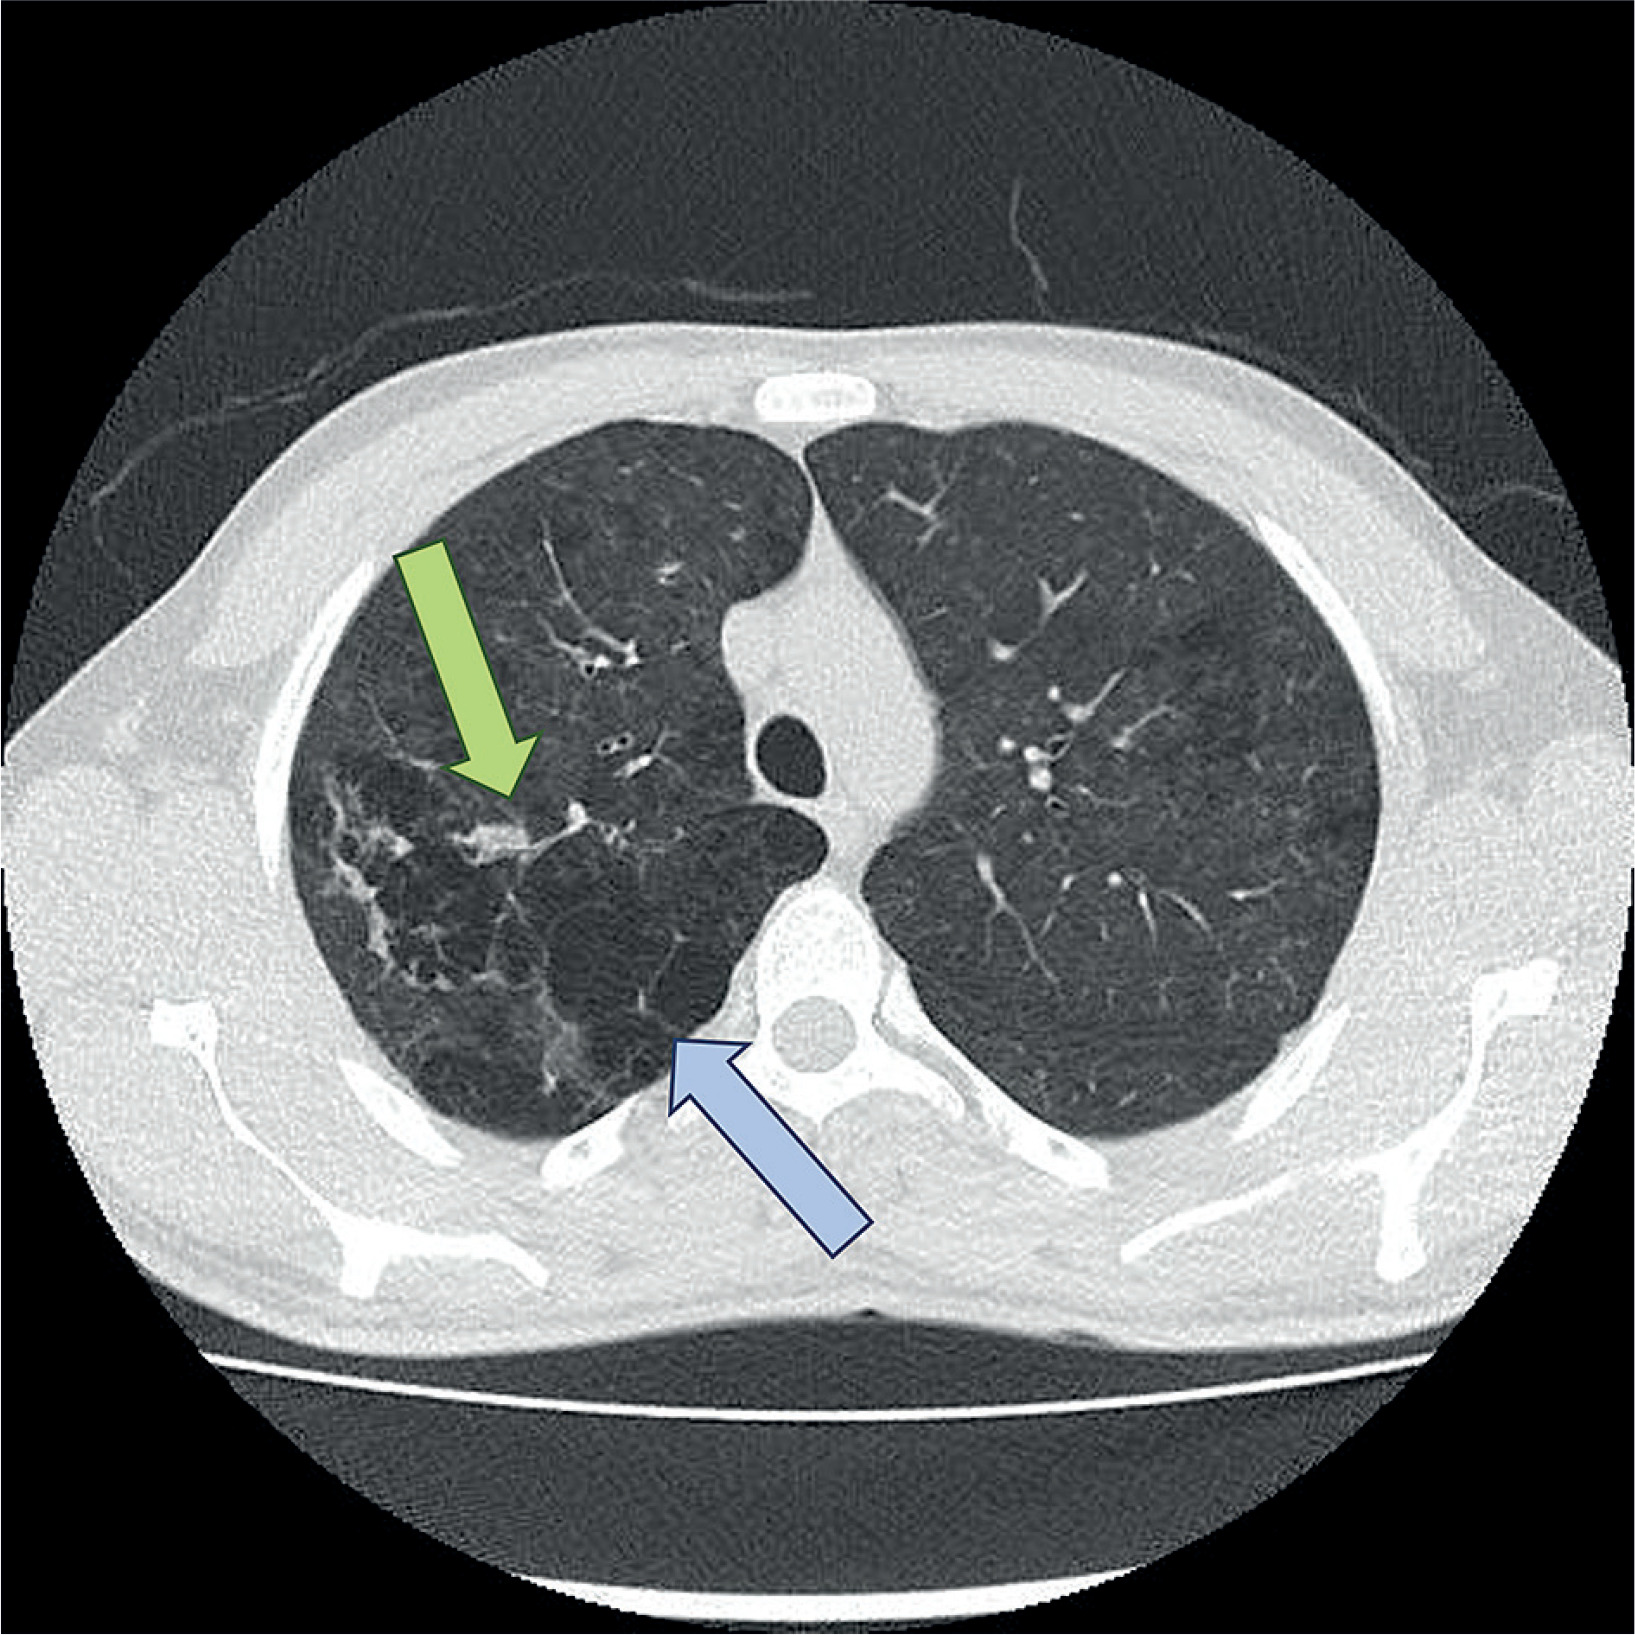

Figure 1

Computed tomography (CT) image demonstrating emphysematous lung parenchyma (blue arrow) and the bleeding site in the bronchial artery (green arrow), identified as the source of hemoptysis